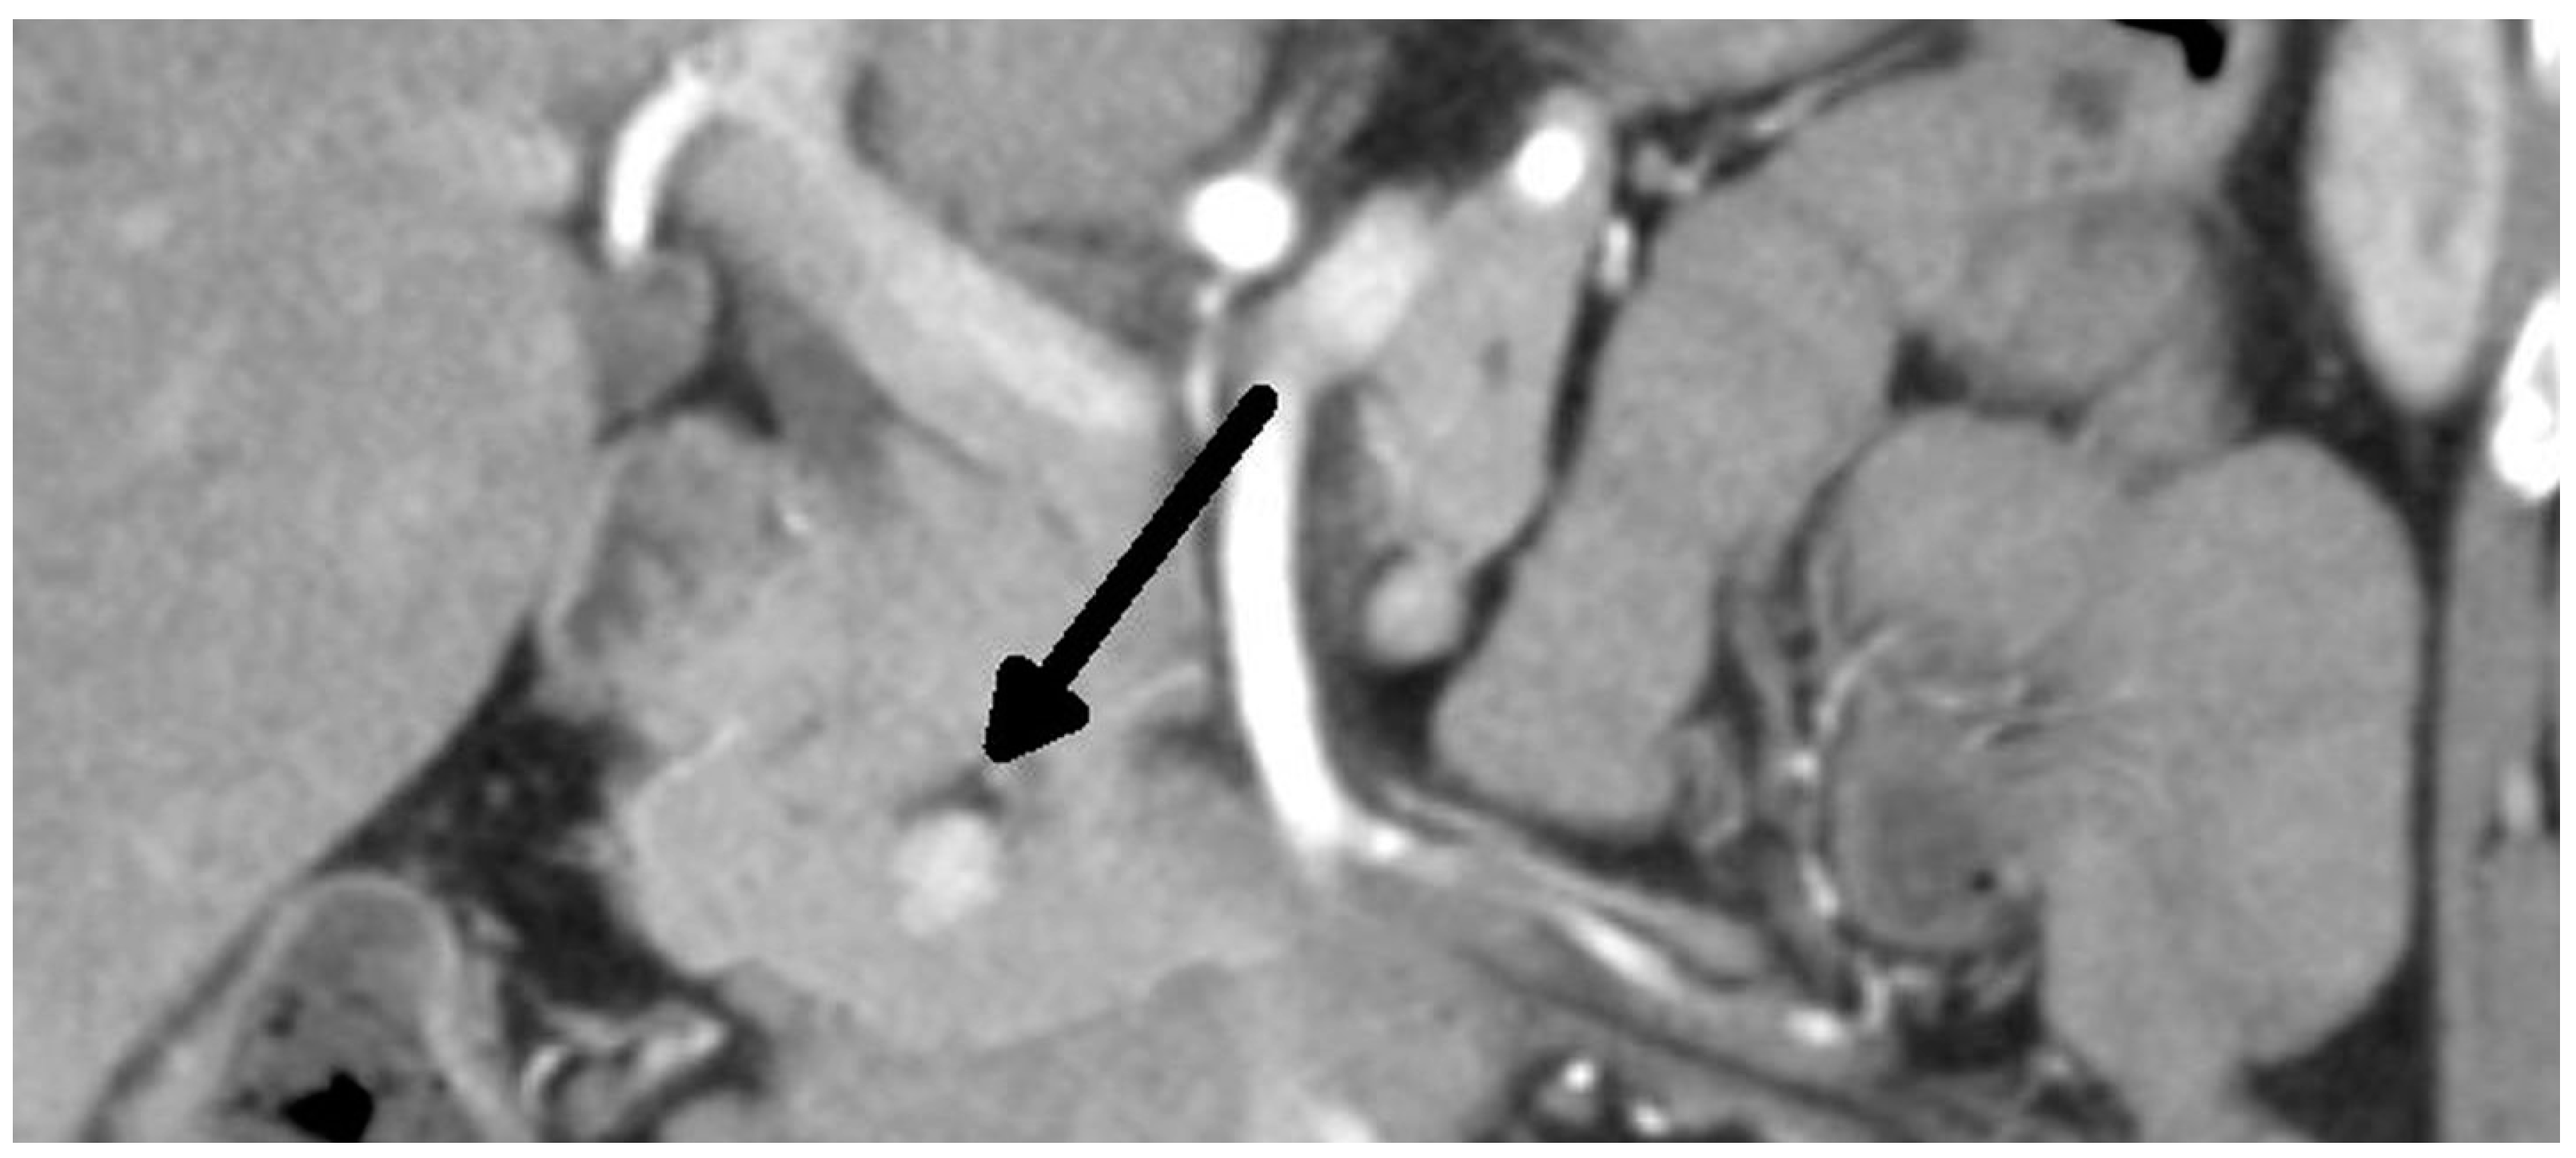

Figure 1.

Insulinoma—CT arterial phase (tumor marked with an arrow).

Overall, we performed a total of 116 scheduled surgeries on patients suffering from insulinoma. The surgically treated postoperative complications are listed separately. There were 79 females, with a mean age of 52 years (20–83 years, median was 51 years), and 37 males, with a mean age of 53 years (29–81 years, median was 59 years). The duration of the symptoms varied from 1 month to 25 years (mean was 3 years). All patients were examined in the 3rd Department of the Inner Medicine General University Hospital (which is focused on metabolic disease), including insulinoma localization. A fasting test was performed on all patients during hospitalization. Additionally, the levels of calcium and phosphates in the serum were examined in all patients, as well as in the hypophyseal region, to exclude MEN I syndrome. Radiological examination depends on the diagnosis period, and CT scan was used in all cases (Figure 1 and Figure 2). This was due to the unavailability of MRI, especially in the first years of the study.

The treatment of choice is surgery. Therefore, it is necessary to establish the precise localization of the tumor. The sensitivity and specificity of radiodiagnostic methods are rising. A conventional CT scan has a sensitivity of about 33%, while that of a single-slice helical CT is 58%, and that of multidetector CT is 75–100% [8]. Insulinomas are hypervascular, so they have greater enhancement during the arterial phase of the examination. The can be said of MRI. A conventional MRI can detect insulinoma in about 31% of cases, and multiphasic MRI can detect insulinoma in 85% of patients [4]. The use of 18 F-fluorodeoxyglucose (18 F-FDG) PET is not helpful in diagnosis due to the low proliferative activities of these tumors. Furthermore, 68 Ga-DOTApeptide PET is also not helpful, because it shows a low expression of SSTR subtype 2 [1]. The 68 Ga-DOTATATE scan is more sensitive for localization [1], but according to other studies, its sensitivity is lower than 20% [9]. Recent data show that 68Ga-DOTA-Exendin-4 PET/CT has better results, with a sensitivity of nearly 85% and a specificity of 100%. Exendin is a synthetic glucagon-like peptide-1, which is expressed in cases of insulinoma [10]. Unfortunately, we do not have personal experience with this method. Contrast ultrasound and endoscopic ultrasound are highly sensitive and specific (90–100%) [1]. All these methods are complementary, not competitive [4]. Despite the progress in diagnostic methods, in some cases, surgery can be indicated without precise knowledge as to the position of the tumor. An experienced surgeon can find the tumor in 42–95% of cases [1,5,11]. Moreover, there are some case reports about the intraoperative near-infrared imaging of insulinomas in the literature [12,13].